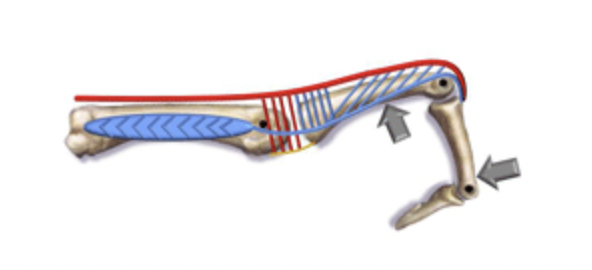

Tommy John Injury: Journey Back to Throwing after a UCL Injury

Anatomy of Ulnar Collateral Ligament (UCL) Originating on the anteroinferior surface of the medial epicondyle of the humerus and inserting onto the sublime tubercle of ...